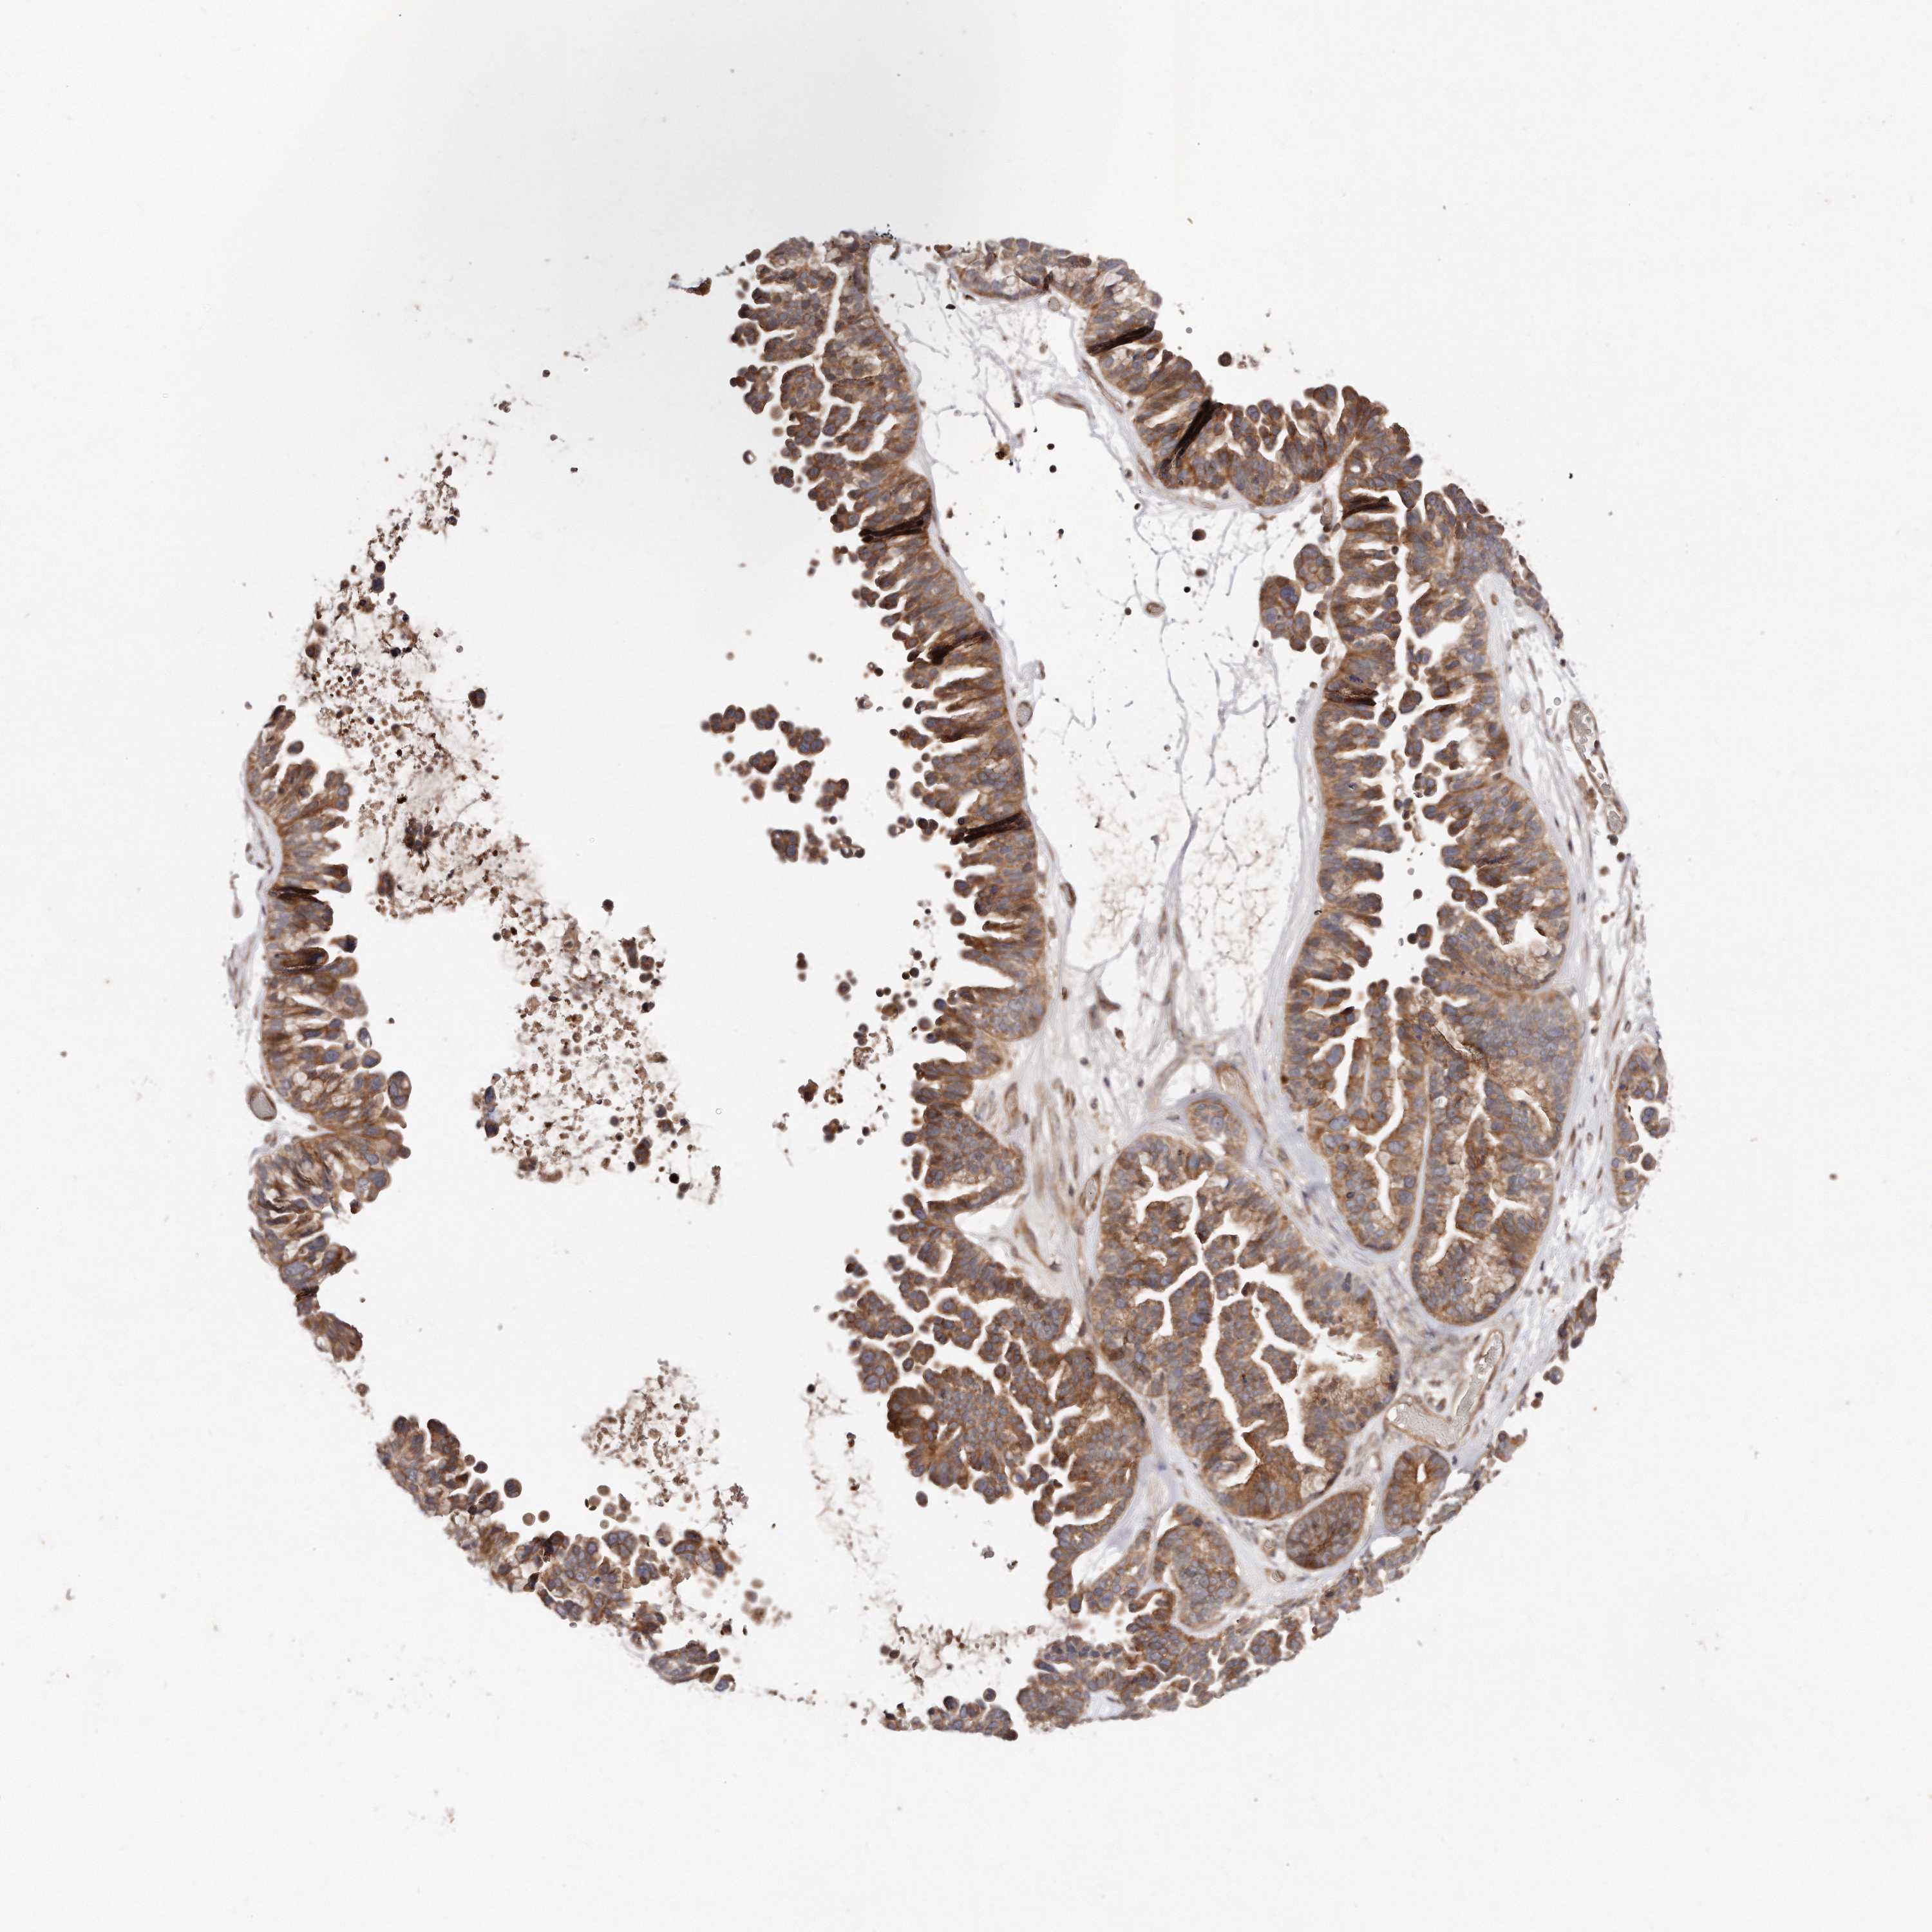

OVARIAN CANCER - Protein expressioni

A mouse-over function shows sample information and annotation data. Click on an image to view it in a full screen mode. Samples can be filtered based on level of antibody staining by selecting one or several of the following categories: high, medium, low and not detected. The assay and annotation is described here.

Note that samples used for immunohistochemistry by the Human Protein Atlas do not correspond to samples in the TCGA dataset.

Antibody stainingi

Antibody staining in the annotated cell types in the current human tissue is reported as not detected, low, medium, or high, based on conventional immunohistochemistry profiling in selected tissues. This score is based on the combination of the staining intensity and fraction of stained cells.

Each image is clickable and will lead to virtual microscopy that enables deeper exploration of all samples and also displays staining intensity scores, fraction scores and subcellular localization as well as patient and tissue information for each sample.

Antibody HPA030101

Staining

High

Medium

Low

Not detected

Intensity

Strong

Moderate

Weak

Negative

Quantity

>75%

75%-25%

<25%

None

Location

Nuclear

Cytoplasmic/membranous

Cytoplasmic/membranous,nuclear

Cystadenocarcinoma, serous, NOS

Carcinoma, endometroid

Cystadenocarcinoma, mucinous, NOS

Carcinoma, NOS